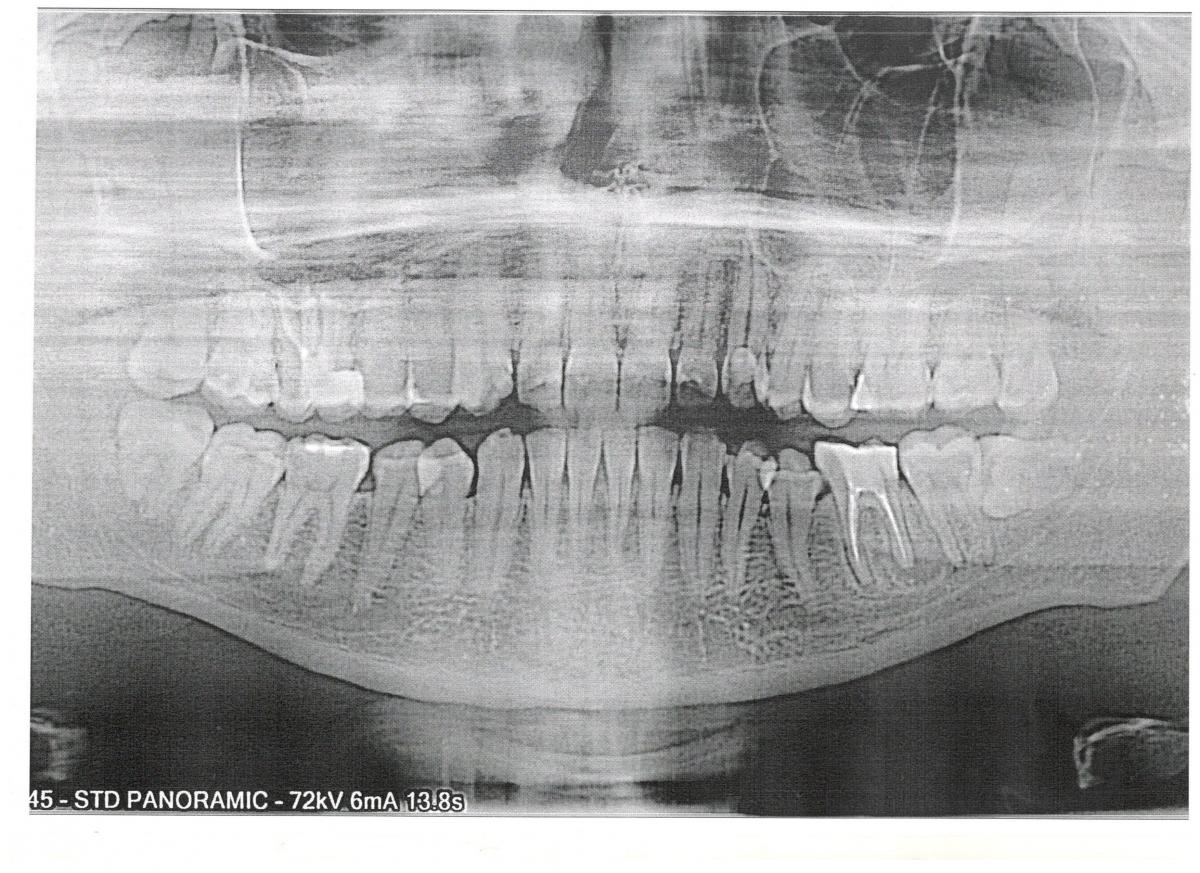

Рентгенологическая диагностика саркомы у кошек

Раздел: Визуальный дайджест